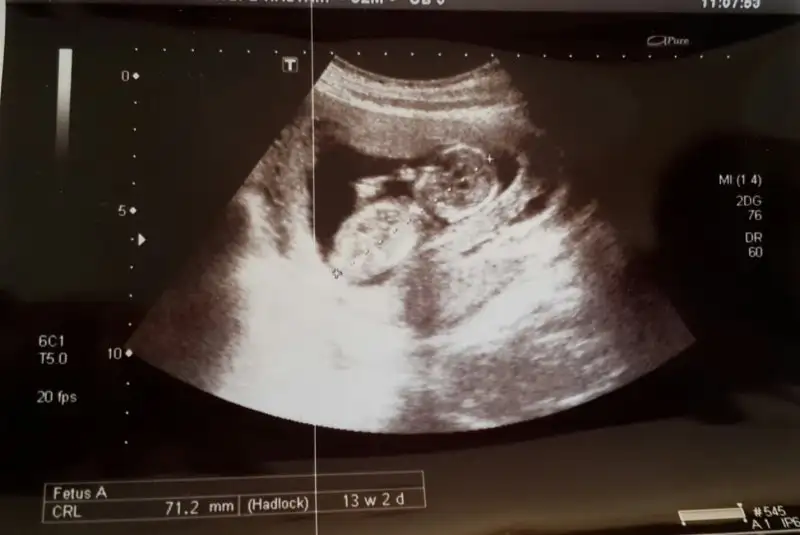

Az önce doktordan geldim 2 li teslimi gösterdim iyi çıkmış. 14 haftalık gözüktü Ultrasonda 3 gün önden gidiyor. ama cinsiyetini göremedi. Cumartesi kendi doktoruma gideceğim. Devlet hastanesindeki ultrason çok net değil. Hayirlisi bakalım ben erkek gibi hissediyorum.

Kızlar hastaneden geliyorum ikili testimi yaptırdım ölçümler iyi çıktı çok şükür hatta bebeğim 1 hafta ileri gözüküyor kan testim 4 gün sonra çıkacak cinsiyet için %90 erkek dedi doktor zaten erkek hissediyordum bakalım kesin değil sonuçta sağlıklı hayırlı olsun inşallah

Boyu 5.5 cm olmuş ense 3 mm yanlış hatırlamıyorsam yeri gayet sağlammış, kemikleri oluşuyor dedi doktor amcamız.cinsiyeti göremem, mümkün değil dedi diğer ayı beklemelisin dedi